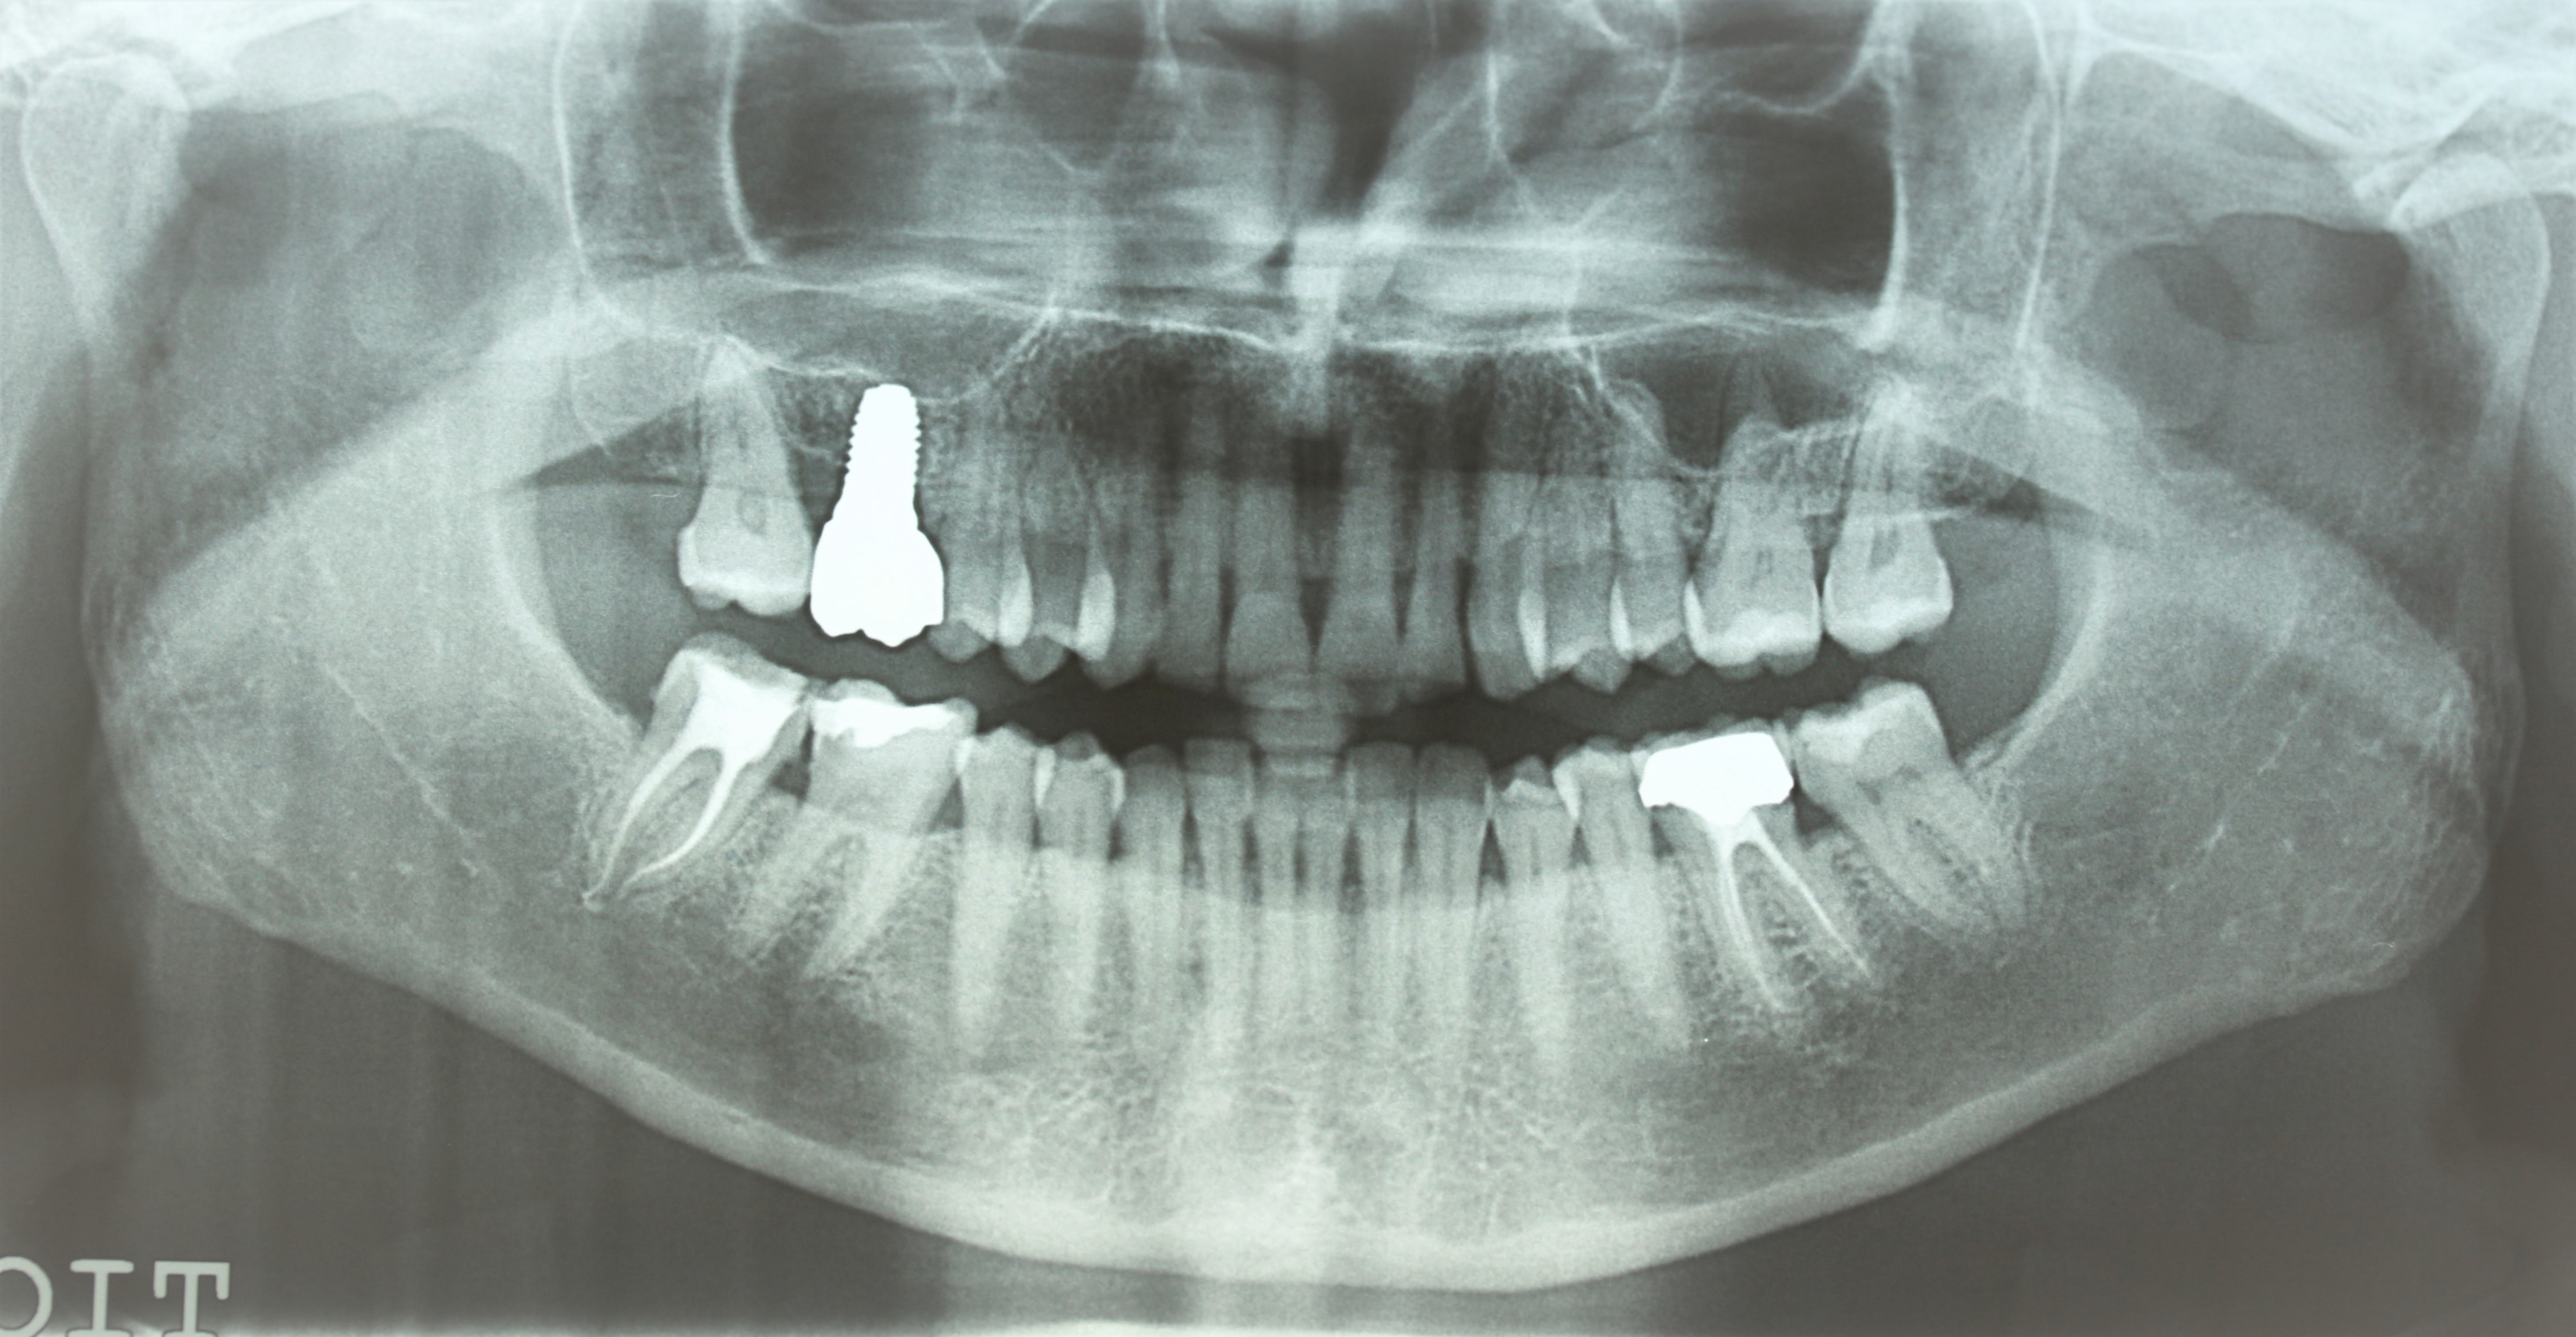

je lui demande de passer une pano que voilà hier aprem .

on voit une tache en region de dds , un artefact ou pb ?

Y'a rien derrière, mais carie distale sur 46 et surtout crado entre 47 et 46, du coup possible que 2 intralig en 2 jours aient inflamé le secteur.

Je verrais bien mortif de 46 à cause de reprise de carie 46d et image apicale à confirmer

trauma occlusal de la 47 qui tape trop fort sur la 16, qui est un implant et pourrait donc amplifier le pb ?

Y'a clairement un truc sur 46D, ça semble la cause la plus probable.

mes radios pourries avant , après endo .

pas évident sur mes radio à la con qu il y ait embrouille en 46 .

certes le compo sur 46 et 47 sont pipés , mais pas plus que ça . je ne sais pas de quand ça date , c est la 1ere fois que je la voyais

ce qui est sur , c est que son dentiste s est aperçu qu il y avait un pb , elle a du distaler sa 47 et perdre son point de contact a cause de sa 16 implantaire , puisqu' il a bricolé un compo en distal de 46 pour fermer l espace .

et donc pour le moment j opterais sur nécrose de 47 du au bruxisme . la 46 sais pas .

Concernant ta dame je vois moi aussi des images louches au niveau des dds...

Peut être un cone beam et en même temps tu fais faire des coupes au niveau de la 6 et la 7?